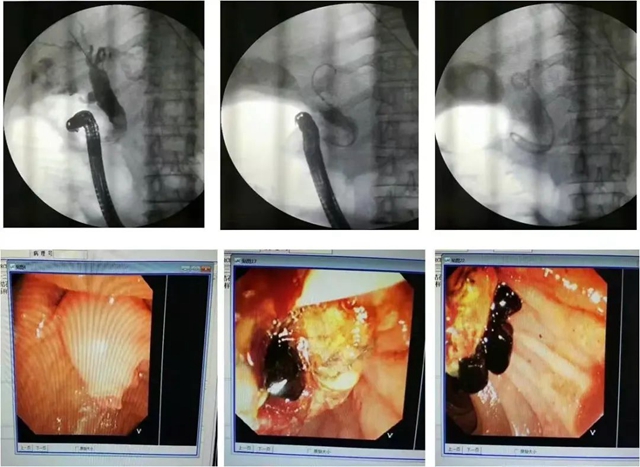

近日,70岁的肖嬢嬢在当地医院诊断为“胆总管结石,梗阻性化脓性胆管炎”,由于身体状况差,病情危重等原因,不适宜进行外科手术治疗。于2022年12月4日,在西南医科大学附属中医医院肝胆胰外科通过ERCP取石引流后,30分钟结石被成功取出。 ...